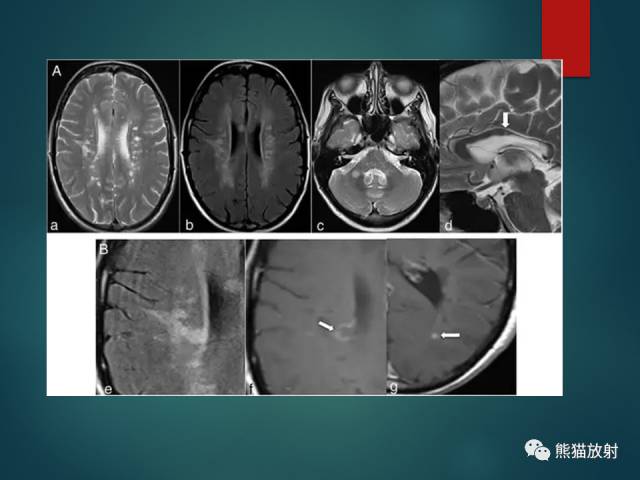

- 多发性硬化(MS):中青年女性;症状发作与缓解交替出现;直角脱髓鞘征;不同时期脱髓鞘斑块表现不一,急性期有强化。

- 脑白质疏松(LA):小动脉病变导致的白质纤维脱髓鞘;T2-FLAIR呈较高信号,DWI无弥散受限;常两侧对称,脑室周围明显。

- 腔隙性脑梗死(LACI):颅内小动脉及穿支动脉狭窄或痉挛;T2-FLAIR呈高信号;DWI急性期弥散受限;基底节、脑干及丘脑多见。

- 血管周围间隙(PVS):与软脑膜下腔相连;分为基底节型、大脑半球型及脑干型;与脑脊液信号相同。